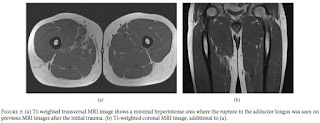

Radiografias convencionais da pélvis e anca direitos não

apresentaram anormalidades ósseas. A ressonância magnética (RM) revelou uma

região de hipersinal intramuscular no adutor longo, com comprimento

craniocaudal de 4,2 centímetros. Não houve retração do músculo.

Com base nos achados clínicos e na ressonância magnética o

O exame de RM adicional mostrou hipersinal subtil em imagens

ponderadas em T1 na zona da rutura anterior do adutor longo, sem quaisquer

anormalidades estruturais. Os achados foram discutidos com o paciente e nenhum

tratamento adicional foi iniciado.